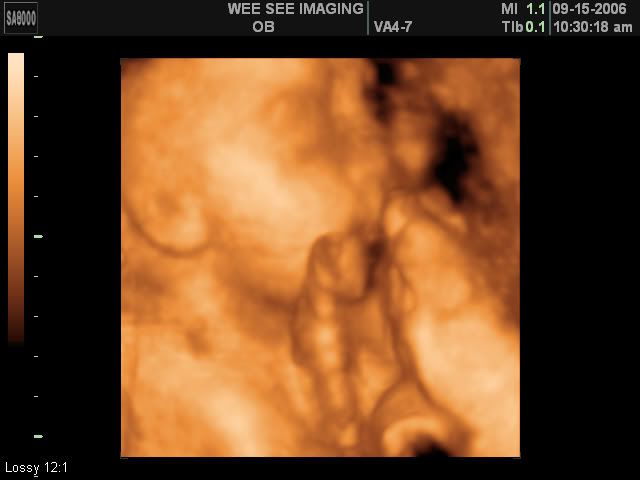

Victoria Rose Kelly

Date Due: December 15, 2006